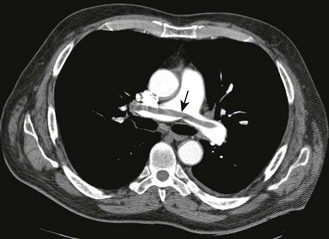

Fig. 7.26 Acid–base diagram.

Acid–base nomogram showing the relationships between pH (H+), PaCO2 and bicarbonate. The bands represent 95% confidence limits of acid–base disturbance.